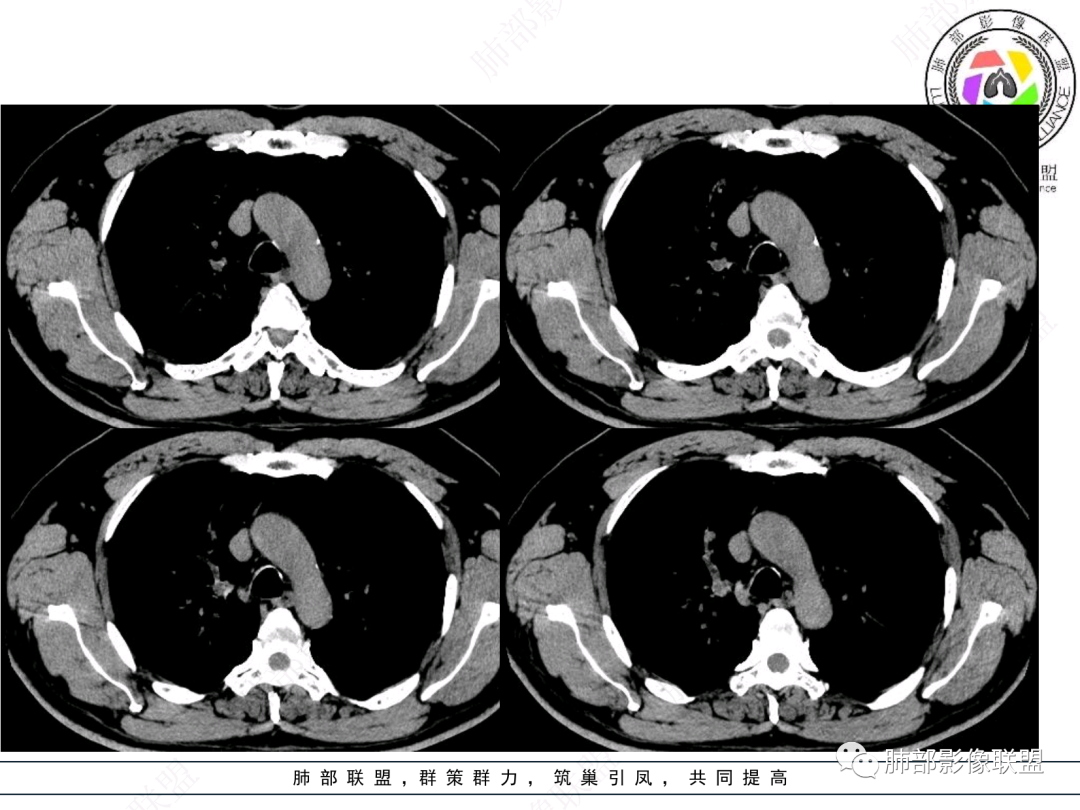

右肺上叶支气管截断,内见软组织密度结节,支气管管壁破坏,病变侵及管外,增强强化明显。右肺上叶沿气管血管束多发斑片影,考虑恶性性病变并阻塞性炎症,鳞癌,神经内分泌肿瘤。

右主支气管及肺门不规则软组织结节,点状钙化,不均匀强化,气管壁破坏,上叶支气管阻塞,分支粘液栓,血管束增粗,沿支气管分布多发结节,考虑鳞癌合并阻塞性炎症,鉴别结核。

男性,52岁,右侧主支气管腔内外占位伴点状钙化,病灶大部分位于腔外,右肺上叶散在结节影,气管腔内病灶,动脉期中度强化,静脉期强化减低,首先考虑气管腔内类癌可能,鉴别鳞癌,肺内病变倾向感染性病变;再有气管结核伴肺内播散。

男,52。间断咳嗽、咳痰2周,加重3天。胸部CT:右主、右上叶支气管多发软组织影,跳跃不连续,内可见小环状高密度,点状钙化,管壁破坏,上叶支气管堵塞,远端分支粘液栓,可见小支气管管壁增厚、管腔狭窄,沿支气管分布多发结节,无大片炎症不张。考虑:TB?NTM?鉴别Ca并阻塞性炎症。

患者中老年男性,咳嗽咳痰2周,无发热、咯血,伴胸闷、乏力及盗汗等,右上叶沿支气管血管束分布结节样变,管壁增厚;右肺门肿块,形态不规则、密度欠均匀,似有钙化,轻强化,主气道下端及右主支气管开口处见新生物,强化不支持类癌,镜下病变形态不大支持腺样囊性癌,考虑鳞癌可能性大,右肺上叶病变结核可能。

腔内肿物,强化不均匀,强化程度为轻中度强化(CT值增加25HU),且强化特点为快进快出,右肺上叶支气管责任区域的阻塞性炎症加痰栓(气管镜也证实右上叶支气管内痰多)。这些均明确指向鳞癌。

屈运良:

这个病例比较好,我们的观察点在哪?这是右上叶支气管病变,需要了解:腔内、壁、腔外、远端,腔内有软组织密度影,近端膨隆。

红色:软骨连续性良好,壁外有软组织密度影,绿色:软骨不连续,破坏了,外面软组织密度影。

南边:提示软骨破坏,也就是病灶腔内朝壁外侵犯了——恶性。

远端支气管腔内不强化的是粘液栓,强化的是肿瘤。

如果在这种情况下临床想通过CT了解啥?主要是:a、与附近结构的关系:血管、淋巴结;b、远端情况;c、其他区域转移情况;

影像上分析的观察点:腔内、壁、腔外、远端,然后就是远端肺组织、淋巴结、肺血管、胸膜、其他肺部,这个人就是阻塞性炎症为主。